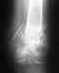

1)Канал от спицы идет через кость, так что гной в кости есть (был).

2)"Спицевой" остеомиелит уже есть, насчет "других осложнений" - уточните, что именно подразумевается.

5)Дренировать канал, промывать его через катетер любыми водными растворами несколько раз в сутки. Течение "спицевого" остеомиелита обычно доброкачественное, процесс локальный, без тенденции к распространению, и даже без лечения зачастую заканчивается выздоровлением. Успехов.